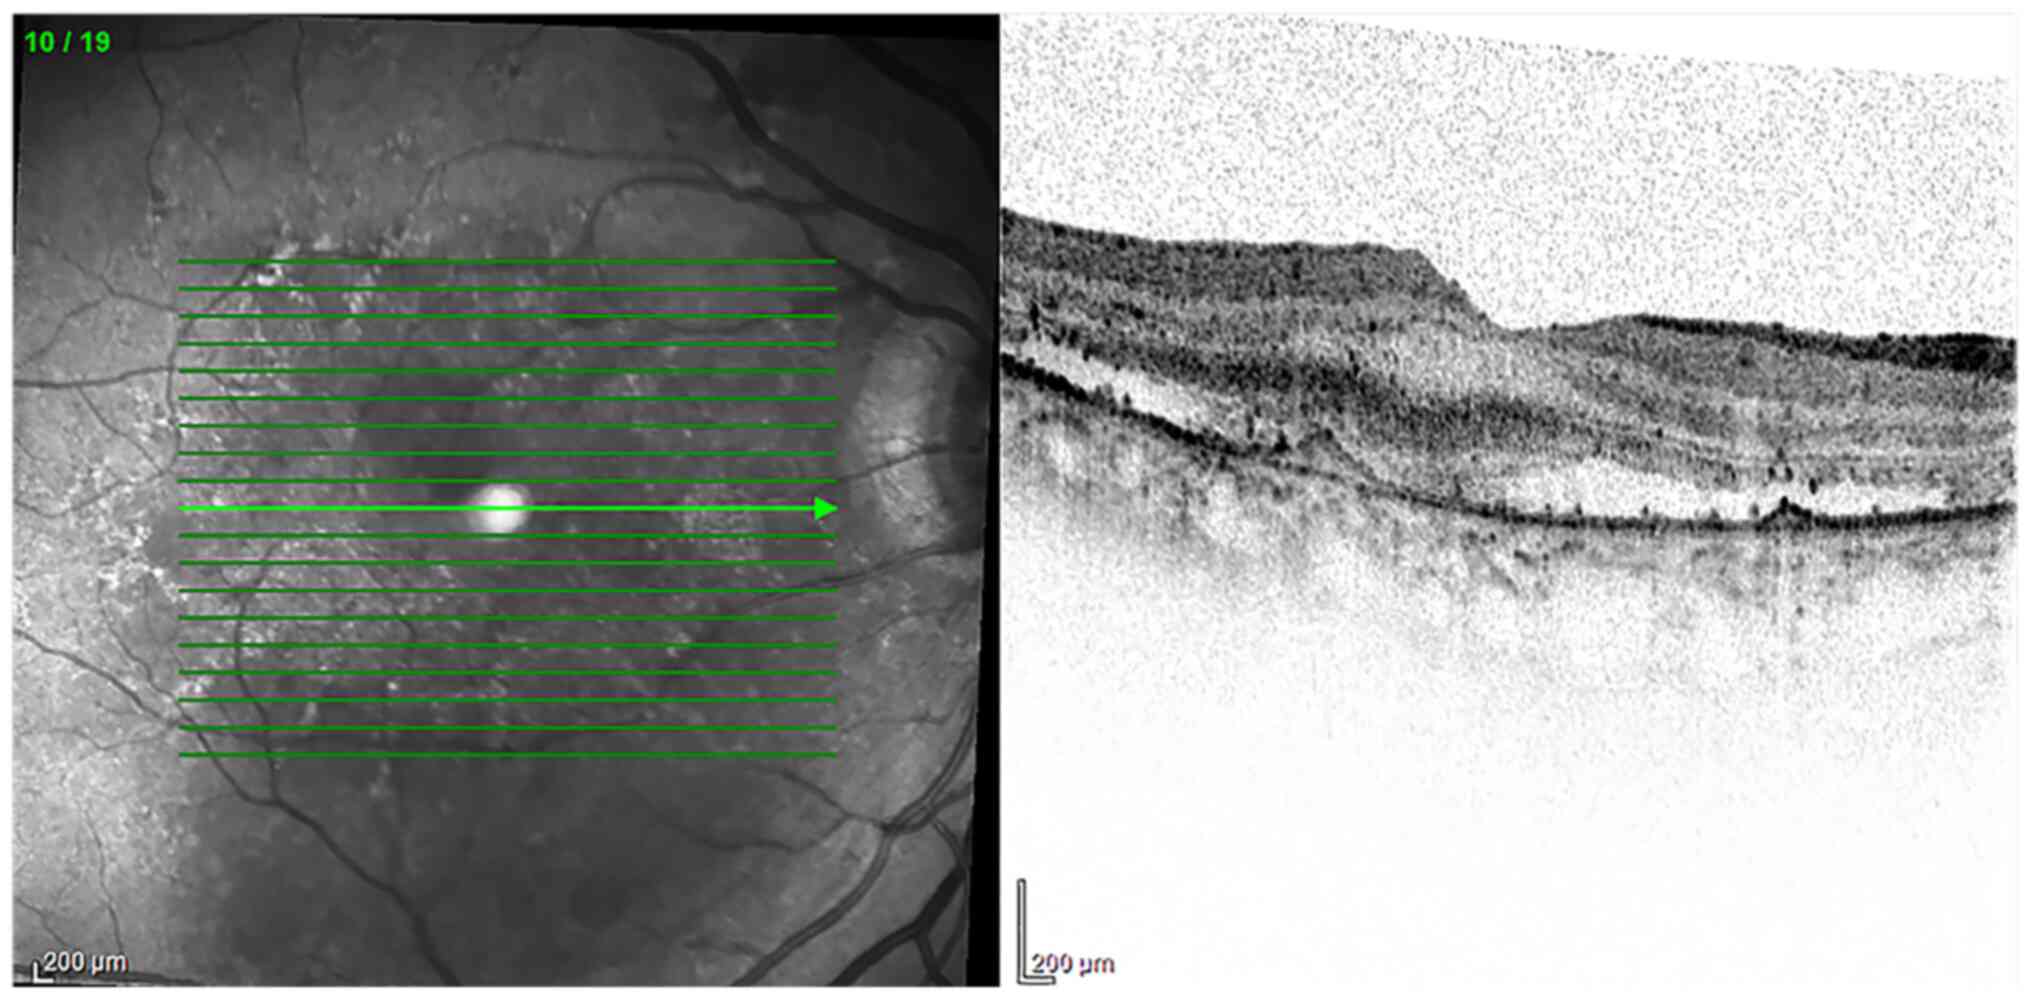

DR is considered to be the main cause of irreversible visual loss all over the world in the working-age population (41). Clinically, it can be defined as a metabolic and microvascular disease (42), characterized by a process of chronic inflammation. Ischemia, microaneurysms, hemorrhages, retinal edema, neuronal degeneration and neovascularization (43) represent the most indicative manifestations of DR (Fig. 3).

Figure 3

OCT. Diabetic retinopathy with cystoid macular edema. OCT showed a retinal section with cystic spaces at the macula. Diagnostic images provided by Professor M. Nebbioso. OCT, optical coherence tomography.